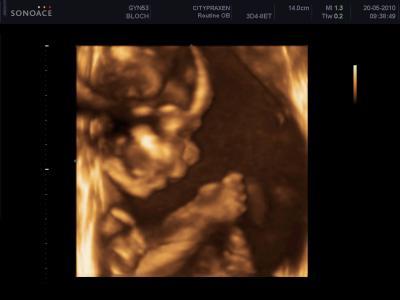

und ich möchte euch gern zwei Bilder von unserem bezaubernen Sohn Leandro zeigen! Er ist so süss und hat auch schön brav mit gemacht! Und ein Daumen nuckler war er heute!

achgott das sind ja soooooooooooooooo süße bilder. wahnsin.